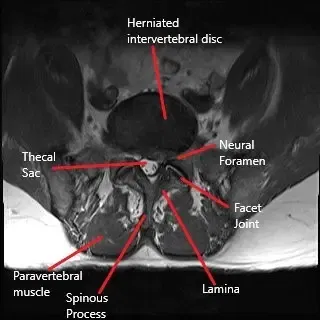

Back pain and radiculopathy may limit a patient’s physical intimacy, so much so they may cease their sexual activity. Microdiscectomy is a gold standard surgery to alleviate symptoms of lumbar radiculopathy due to herniated intervertebral disc. However, a symptom most commonly not discussed after the surgery is the resumption of sexual intimacy.

Healthy sex life is an essential predictor of a patient’s wellbeing. Back pain with radiculopathy due to herniated intervertebral disc commonly hampers a patient’s sex life. Pain during sexual activity as well as the anticipation of pain, both play in dissatisfaction during sex. Some patients may cease all sexual activity secondary to discomfort which may only add to the emotional aspect of radicular back pain.

Microdiscectomy surgery is a minimally invasive surgery performed with an operating microscope or an endoscope. The minimum invasive nature of the surgery leads to less cutting of the muscles and tissues while accessing the disc. The smaller incision also leads to less formation of fibrotic tissue after the surgery. The patients undergoing microdiscectomy are able to return to work and their day-to-day activities sooner than an open approach surgery.